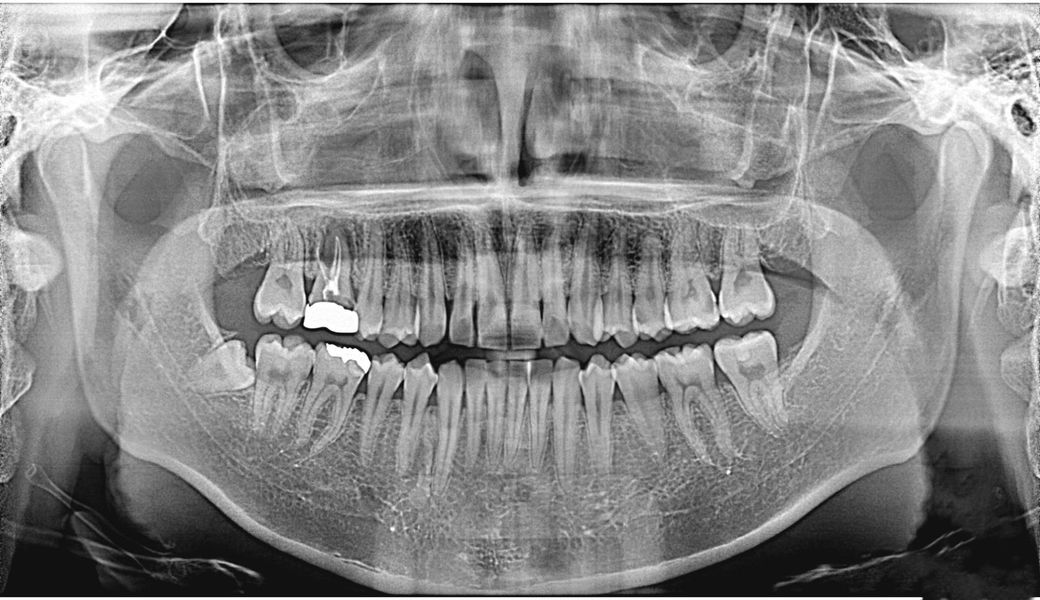

• 2번 째 사진

현재 임플란트 급해서 임플란트 하고있는 치과 인데요, 발치 하고 플리퍼 본 까지 떴는데, 그 외 나머지 충치 들?? 치료까지 진행하려고 하였습니다. 근데 약간 인레이와 크라운쪽으로 좀 몰아가는 보철? 식 치과인 거 같아서요. 열심히 찾아보면서 느낀 건. 인레이와 크라운이 최선인 경우도 있다곤 하지만, 제가 듣고, 보기엔+유튜브 열심히 찾아도 봤는데 보전식 치료가 암만 생각해도 맞는거 같아서 나머지 이빨들은 레진이나, 레진 (빌드업) 치료로 다 받고싶은데 가능한가요 ?

• 오른쪽 6은 어제 발치 하였습니다.